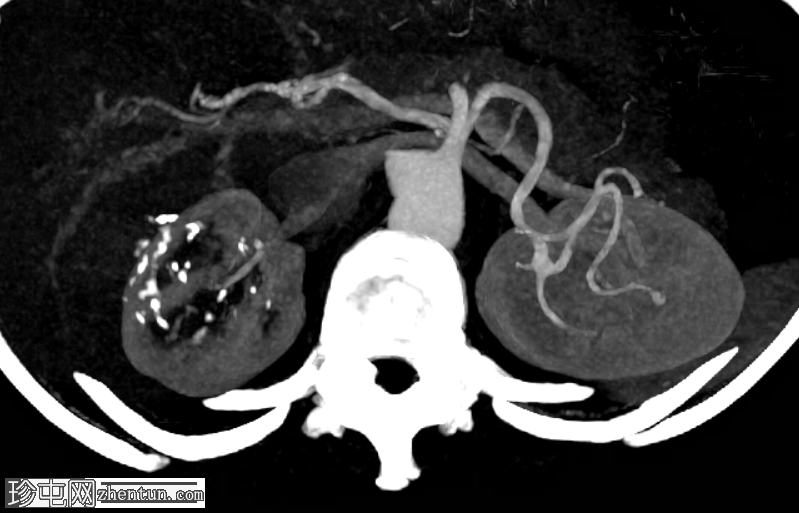

轴位增强扫描

门静脉期

右肾上极前外侧可见一边界清晰、分叶状、部分外生性病变,大小约4.0 x 6.8 cm(轴位)。病变内侧为无强化囊性成分,直径2.3 cm(动脉期和门静脉期平均密度均为13 HU);外侧为强化实性成分,直径4.5 cm(动脉期和门静脉期平均密度分别为68 HU和78 HU)。病灶内可见多处小钙化灶。病灶毗邻肝右叶,但未见侵犯肝实质的证据。肾静脉和下腔静脉通畅。肾门水平可见数个小的主动脉腔静脉淋巴结和腔静脉后淋巴结,其中最大的腔静脉后淋巴结短轴直径为7毫米。

右肾中极前缘可见10毫米Bosniak II型囊肿,双侧肾盂旁可见囊肿。右肾下极可见两处肾皮质缺损。肝脏第8段可见5毫米囊肿。未见远处转移。L2椎体可见血管瘤。